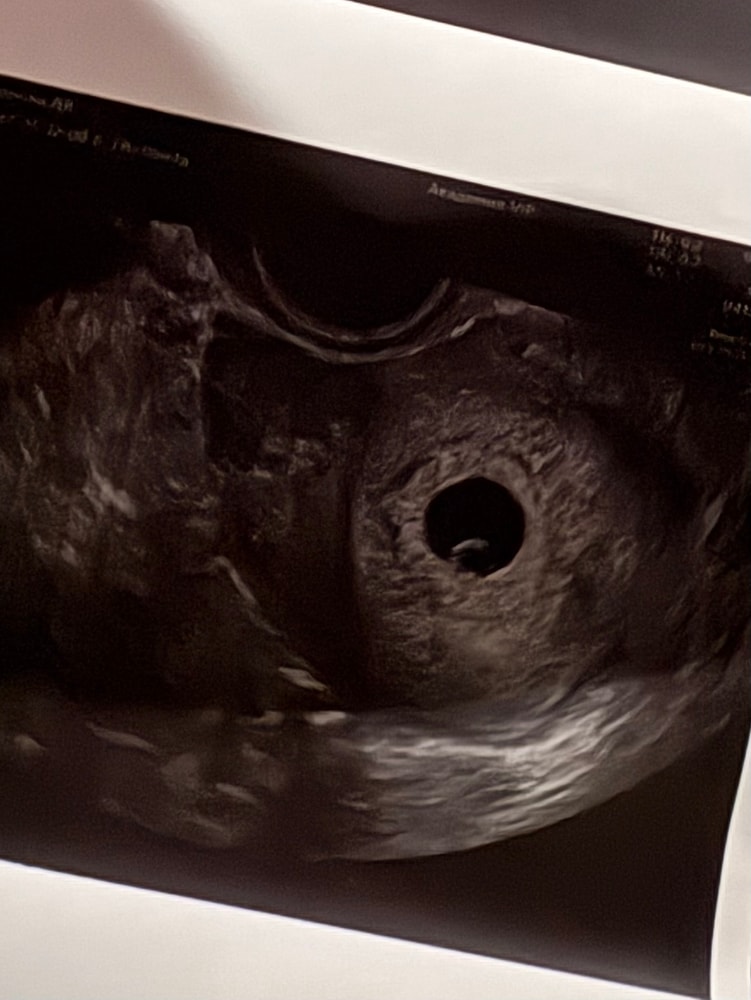

Вот теперь я понимаю, УЗИ хорошее

Девочки привет) я писала 05.12 делала первое узи в жк. Информации очень мало и сделано было секунд за 40 максимум. Сказала что отстает от акушерского срока. Я прикреплю это узи(первое фото первого узи). Сегодня 10.12 сходила в Скандинавию, всё хорошо, на огромном мониторе посмотрела на свою ляличку 🥹, всё расписали, всё показали, как же круто🩷🩷🠼/p>